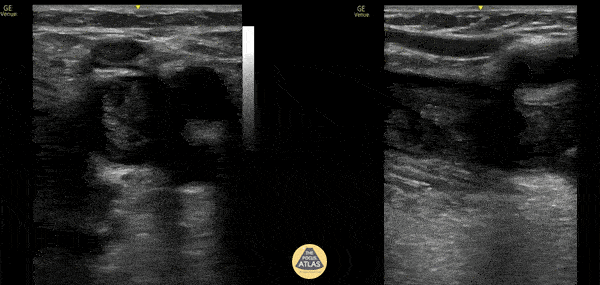

Vascular - Free Floating DVT

71 year old male presented to the ED complaining of left leg pain. POCUS revealed free floating DVT in common femoral vein extending down to the popliteal vein. Free floating DVTs, especially those greater than 5cm, can increase a patient’s risk of developing a pulmonary embolism. Common femoral vein in transverse (left) and sagittal (right) views demonstrate a hyperechoic thrombus that is noncompressible with surrounding anechoic fluid suggesting free floating thrombus with circumferential blood flow. Cite: Chernukha L, et al. Danger of floating venous thrombosis: myth or reality? Phlebology. 2023 Jun;38(5):322-333. doi: 10.1177/02683555231169507. Epub 2023 Apr 20. PMID: 37078365.'] Anthony Elias, DO; Brian Tang, DO; Mike Olshansky OMS-IV, Josh Greenstein, MD; Simone Rudnin, DO